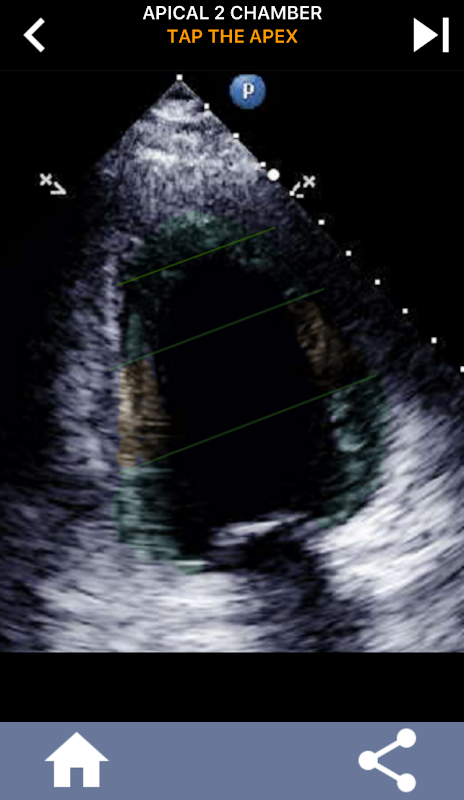

มันเป็นสิ่งสำคัญสำหรับ echocardiographers อัลตราซาวนด์ที่จะเรียนรู้การแบ่งส่วนหัวใจอเมริกันสมาคมหัวใจช่องซ้ายเป็น 17 ส่วนซึ่งเป็นมาตรฐานที่ใช้กันอย่างแพร่หลายโดยรังสีถ่ายภาพอื่น ๆ เช่นการถ่ายภาพด้วยคลื่นสนามแม่เหล็ก, การทดสอบนิวเคลียร์หัวใจ ฯลฯ ของกลุ่มและฟังก์ชั่นที่ได้รับผลกระทบ หลายครั้งที่คนอ่านเสียงสะท้อนของคุณจะถามว่า "คุณเห็นอะไร" และการตอบกลับด้วยตำแหน่งที่แน่นอนของพื้นที่ที่ได้รับผลกระทบเป็นสิ่งที่คาดหวัง

แอพนี้มีมุมมอง echo ทั้งหมดที่แสดง myocardium ที่แบ่งกลุ่ม AHA และจะตอบคำถามคุณเพื่อแตะส่วนที่ถูกต้อง โดยส่วนตัวแล้วฉันพบว่าการสอบย่อยแบบทำซ้ำได้ผลดีที่สุดสำหรับฉันเมื่อฉันต้องการเรียนรู้ / จดจำหัวข้ออย่างรวดเร็ว หากคุณเป็นนักเรียนอัลตราซาวนด์ที่เรียน echo / TTE ฉันคิดว่านี่จะเป็นส่วนเสริมที่ยอดเยี่ยมสำหรับการเรียนของคุณ